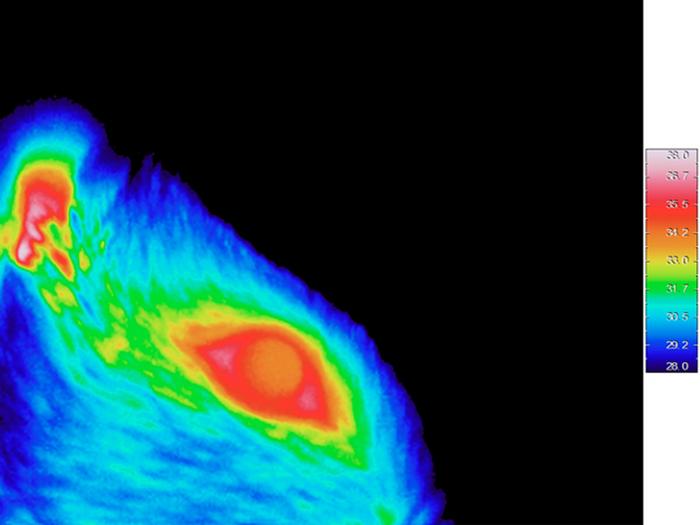

To carry out this study, the researchers used electrophysiology techniques, which allowed them to explore the physiology of tissues and synaptic connections in living beings. To observe trigeminal, thalamic, and cortical activity in response to different stimulation modalities, the authors took recordings of rats while they administered eye drops of different temperatures, which allowed them to test five sensory modalities: intense cold, light cold, neutral temperature, light heat, and intense heat, the later capable of causing a sensation of pain.